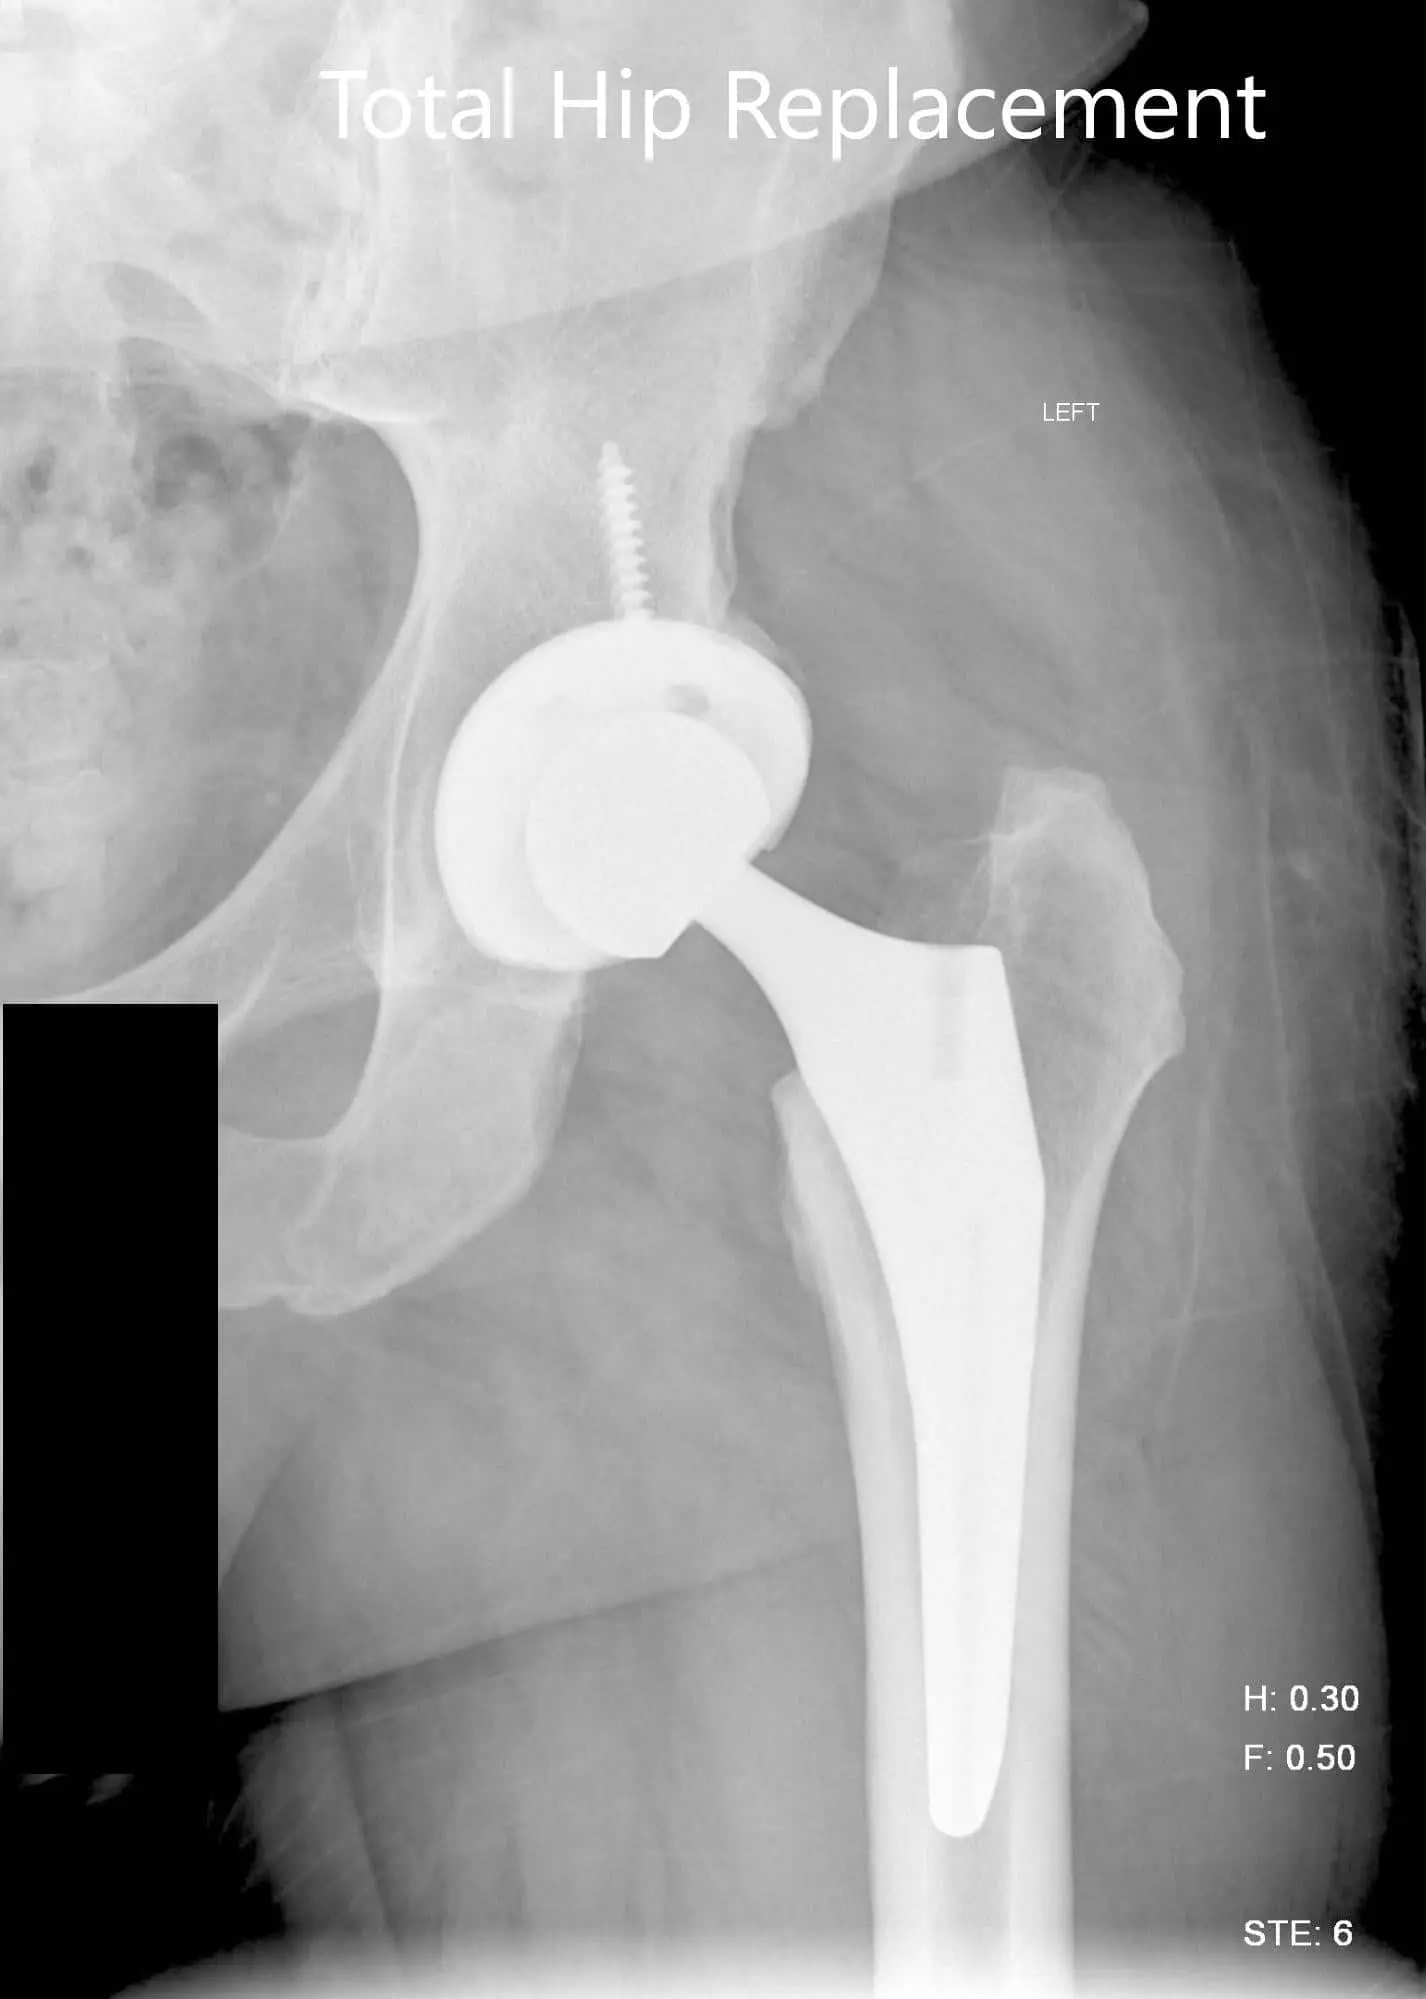

Implant used: Titanium hemispherical shell 60 mm with a 6.5 cancellous screw, 6.5 mm in diameter, 35 mm in length with ceramic femoral head 36 mm, 0-degree polyethylene with 127-degree neck angle hip stem size 5.

Postoperative X-ray images showing AP view and frog legged lateral view.